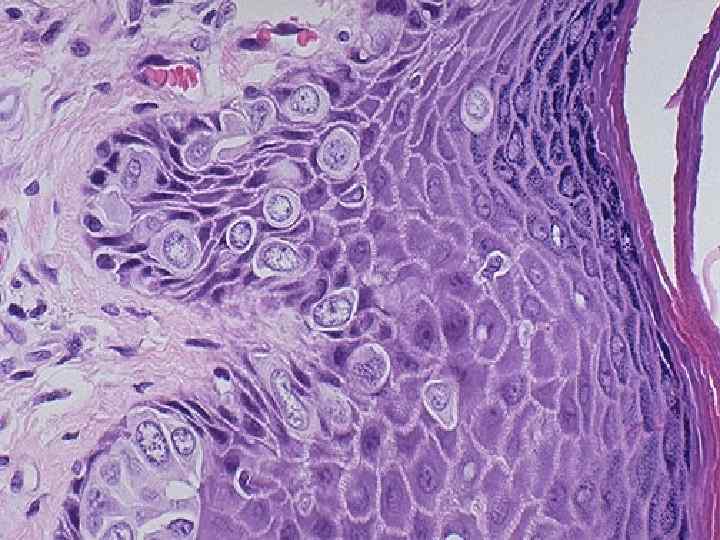

Лейкоплакия слизистой оболочки шейки матки

Рак шейки матки n Рост – экзофитный Гистологически – плоскоклеточный рак n